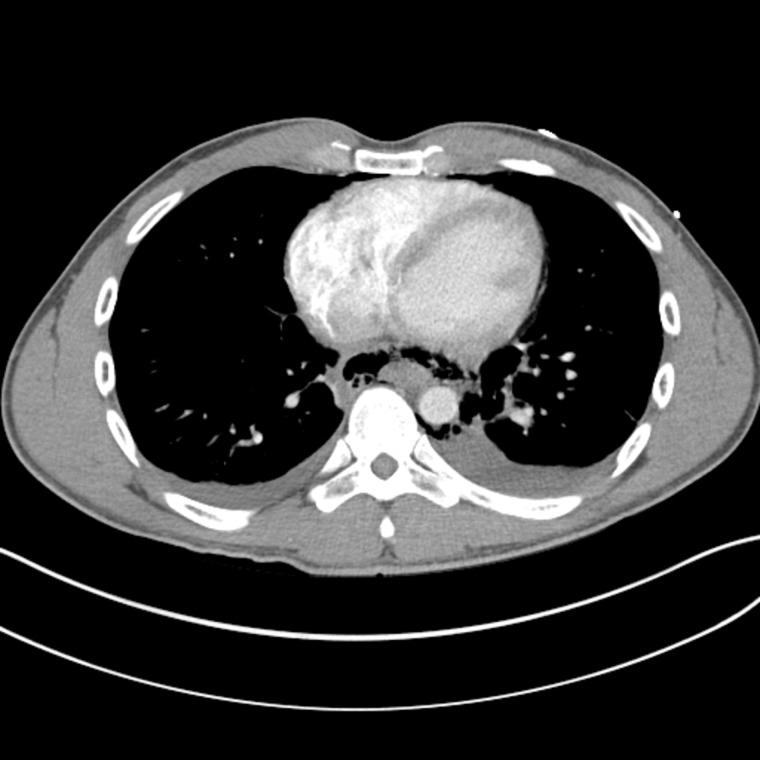

Eosinophilic esophagitis (EoE) is a rare disease of the esophagus that is characterized by eosinophilic infiltrate within the esophageal mucosa resulting in chronic inflammation and stenosis. It typically presents with symptoms of esophageal dysfunction with dysphagia and food impaction being the most common presenting complaints. Herein we describe a rare case presentation of a young patient with spontaneous esophageal perforation in the setting of undiagnosed EoE. We suggest that the placement of a covered esophageal stent can provide full closure of the perforation and restoration of the integrity of the GI tract without the need for more invasive open repair. The patient had a short recovery time with no reported postoperative complications upon 30 months follow up. We believe that it's important to consider and rule out EoE in patients with a history of dysphagia and esophageal perforation.

嗜酸性粒细胞性食管炎(EoE)是一种罕见的食管疾病,其特征是食管黏膜内嗜酸性粒细胞浸润,导致慢性炎症和狭窄。它通常表现为食管功能障碍的症状,吞咽困难和食物嵌塞是最常见的主诉。在此,我们描述了一例年轻患者在未诊断出EoE的情况下发生自发性食管穿孔的罕见病例。我们认为,放置带膜食管支架可以完全封闭穿孔并恢复胃肠道的完整性,而无需进行更具侵入性的开放修复。该患者恢复时间短,在30个月的随访中未报告术后并发症。我们认为,对于有吞咽困难和食管穿孔病史的患者,考虑并排除EoE很重要。